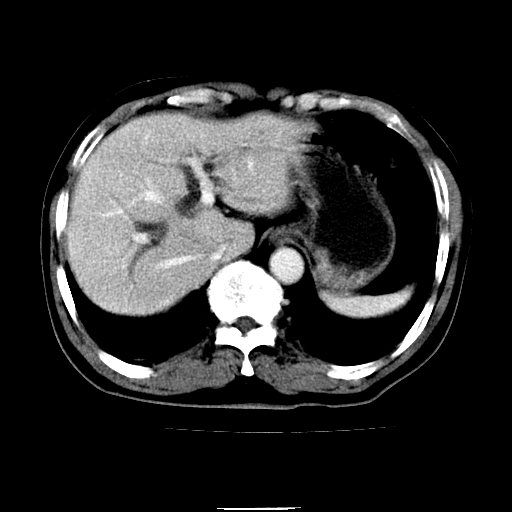

以下是引用chenqiong在2010-3-25 20:56:00的发言:[br]1、胆囊炎,胆囊息肉[br]2、肝内胆管及胆总管扩张,胆总管下端结石[br]3、十二指肠乳头旁憩室

以下是引用zxl51642在2010-3-26 10:47:00的发言:[br]胆囊炎,胆囊息肉,胆总管扩张,但未看到明显肿块,肝内胆管扩张不像恶性,炎性狭窄或阴性结石可能吧,建议mrcp,右肾小囊肿